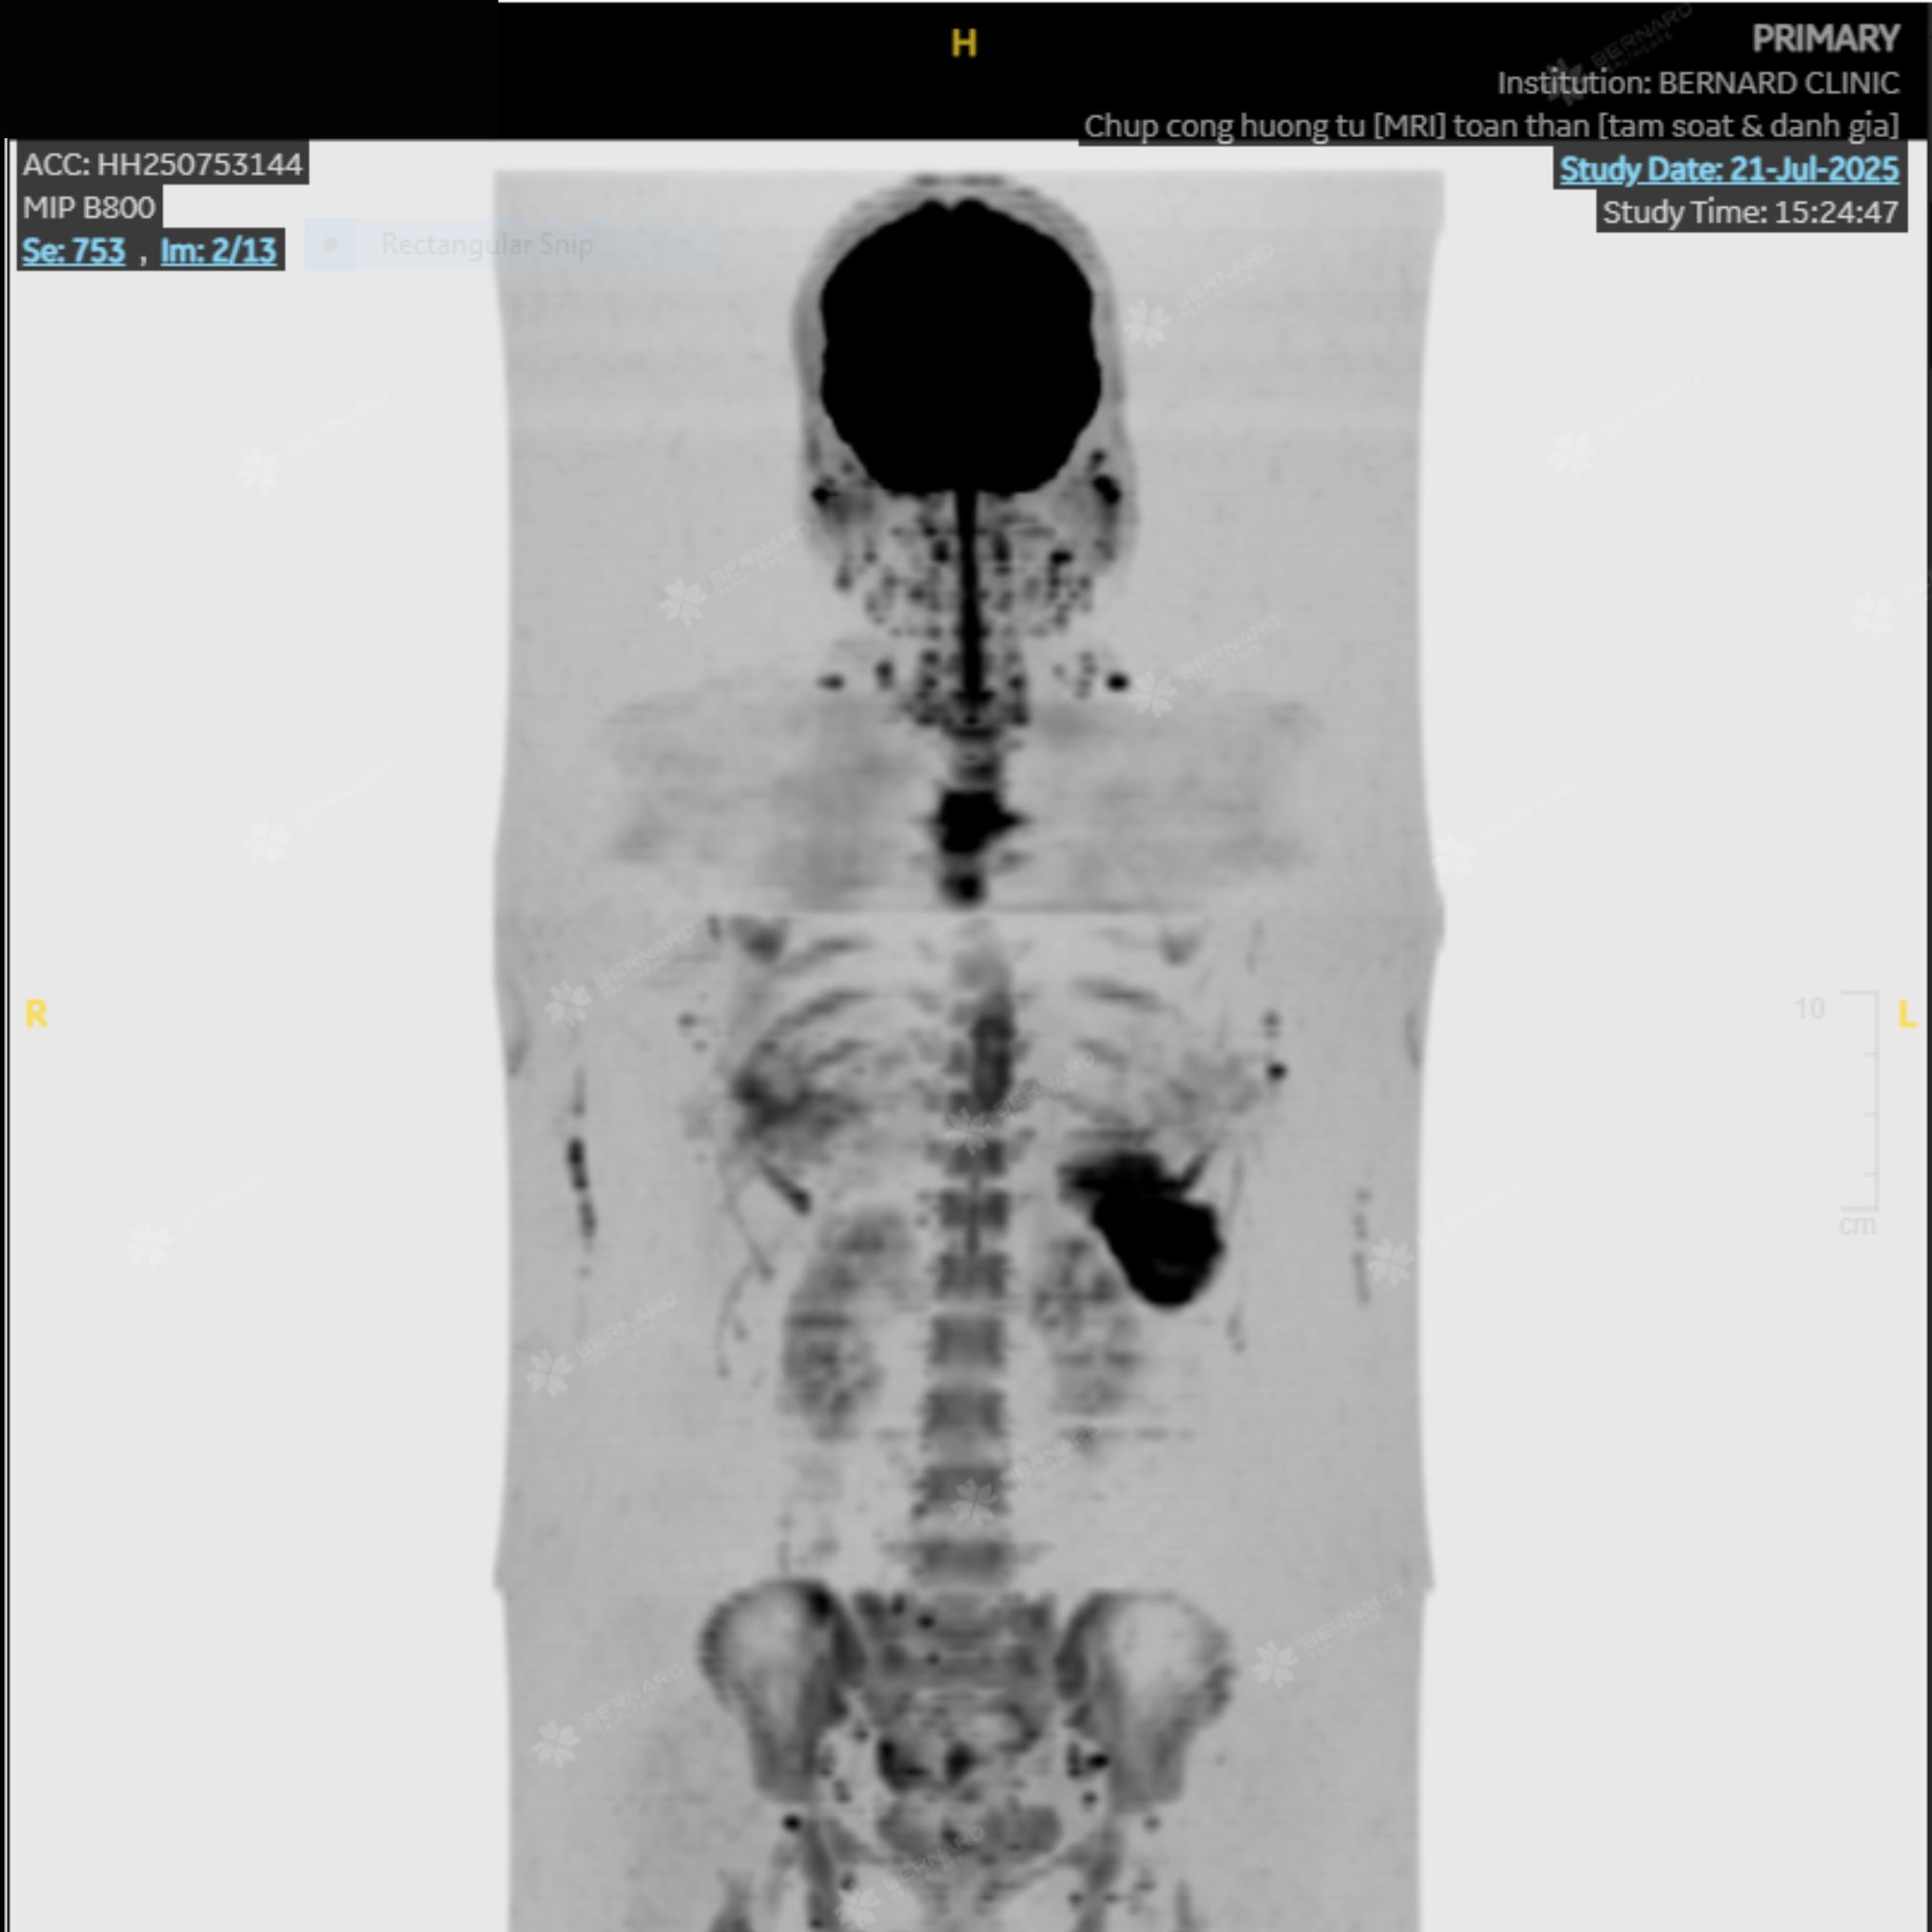

Kết quả MRI toàn thân ghi nhận thay đổi tín hiệu tủy xương tại nhiều vị trí như cột sống, xương sườn, xương chậu, đầu trên xương đùi và vùng lách. Những đặc điểm hình ảnh này gợi ý tăng sản tủy xương (bone marrow hyperplasia) - tình trạng tủy hoạt động mạnh hơn bình thường.

Đây có thể là dấu hiệu của một số bệnh lý huyết học, trong đó có nhóm bệnh tăng sinh tủy, nhưng cũng có thể gặp ở các tình trạng lành tính như thiếu máu mạn hoặc viêm kéo dài.

Theo quy trình Ningen Dock chuẩn Nhật, toàn bộ hình ảnh MRI của chị được kiểm tra chéo bởi chuyên gia Bệnh viện Đại học Yamanashi (Nhật Bản). Báo cáo phản hồi đồng thuận với nhận định ban đầu và khuyến nghị bệnh nhân tiếp tục được đánh giá bởi chuyên khoa huyết học để làm rõ nguyên nhân.

Hiện công thức máu của chị vẫn trong giới hạn bình thường. Tuy nhiên, bác sĩ cho biết tăng sản tủy xương là bất thường cần theo dõi sát để không bỏ lỡ giai đoạn rất sớm của bệnh lý huyết học nếu có.